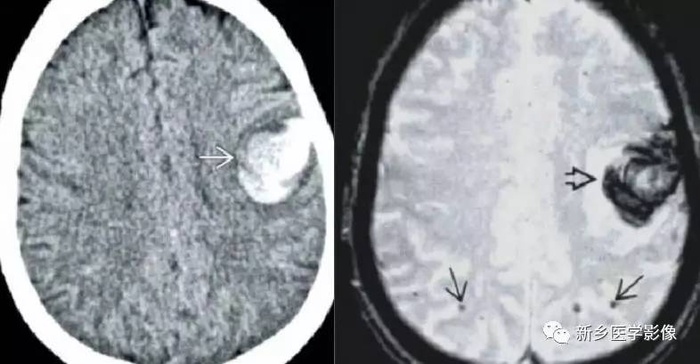

【读片】左侧尾状核头病变ct,mri(结果公布:左基底节脑出血) [病例帖]